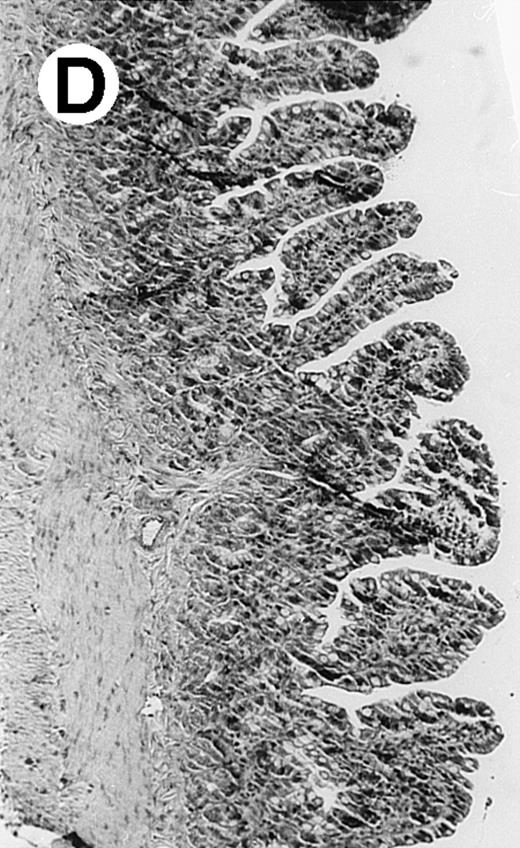

Pathologic findings in the small and large intestine were strikingly different depending on the treatment group. Figure 2A shows a representative pathologic sample from an animal assigned to the control group. Marked thinning of the bowel wall and extensive areas of epithelial cell sloughing was noted. Animals randomized to rhG-CSF treatment had minimal improvement in histologic findings with focal regions of preserved epithelium (Fig2B). Animals randomized to the rhIL-11 group showed substantial improvement with thickening of the epithelial layer and preservation of mucosal cell integrity (Fig 2C). Animals receiving both rhG-CSF and rhIL-11 had the most favorable histologic findings with normal mucosal thickness, minimal inflammatory changes, and preserved tissue architecture (Fig 2D). The composite analysis of the gastrointestinal pathology is provided in Table 1.

Histopathology of small intestinal mucosa cut in transection from an animal in each treatment group (study day 8). The upper panel (row 1) is a low power view (original magnification × 57); the lower panel (row 2) is a high power view (original magnification × 144). Note the diffuse thinning and necrosis of the mucosa with sloughing of intestinal epithelial cells in the control animal (A). There is progressive recovery of the thickness of the mucosa, reduction in inflammatory changes, and improved epithelial architecture with rhG-CSF (B), rhIL-11 (C), and combination therapy with rhG-CSF+IL-11 (D).